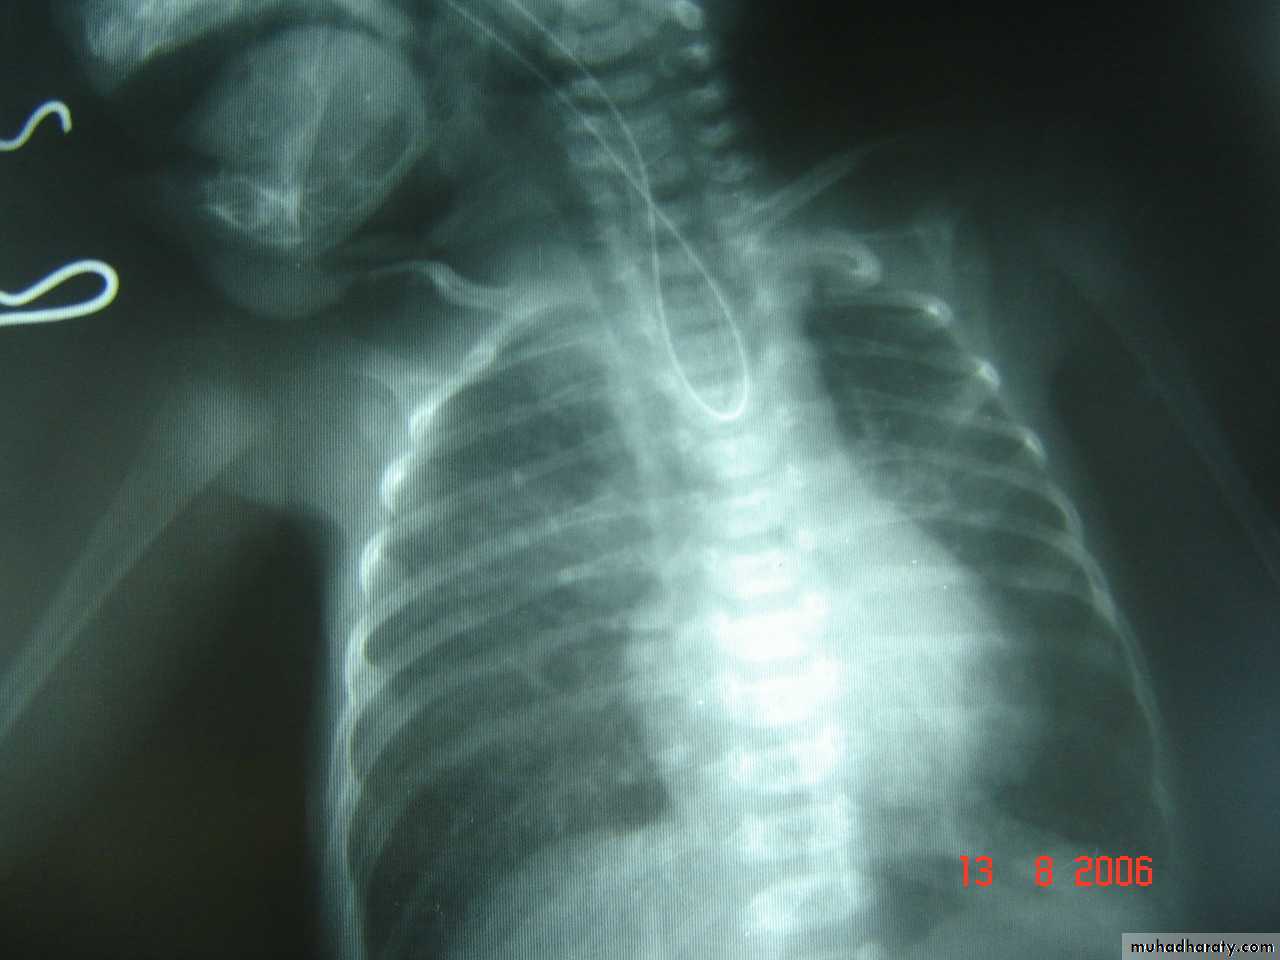

Slide 17Severe chest trauma by car accident1- What does the x ray show?2- What make the neck veins distended